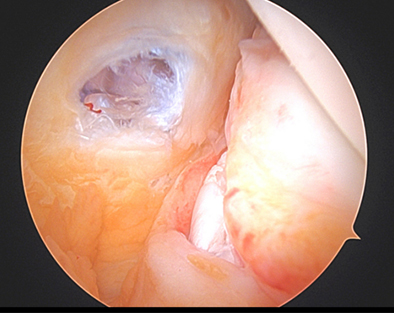

Figure 2

As such, during a diagnostic arthroscopy at the very beginning of an ACL reconstruction, is important to look closely in the back of the knee near the attachment of the posterior horn of the medial meniscus to see if there is a disruption in the capsule. If there is a tear in this capsule region, it is debatable on which ramp tears are considered stable versus unstable. Nonetheless, it is important to discuss your surgeon's approach to ramp lesions and threshold to repair them. In our practice, we repair nearly all ramp lesions identified during the diagnostic arthroscopy. In fact, Dr. Momaya’s team has published a novel anchor based technique for ramp repair. Figure 2-4 demonstrates the repaired ramp lesion in a collegiate football athlete via a lasso and suture technique.